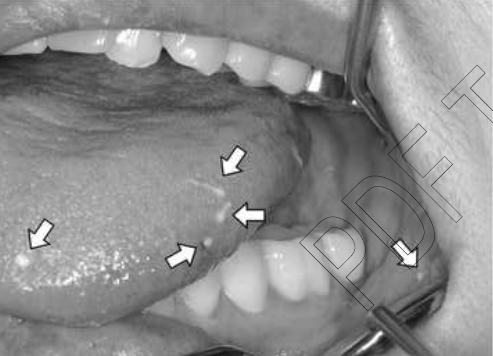

생식 기능이 없는 어린 암컷은 우선 입 주변에 이것을 저장하는데, 이 때 사람이 섭취하게 되면 정포 또한 먹게 된다. 그런데 정포는 사람의 혀나 잇몸을 암컷으로 착각해 침투한다.

이렇게 된다면 정포를 하나하나 ‘핀셋’으로 뽑아야 한다니 매우 주의가 필요하다.